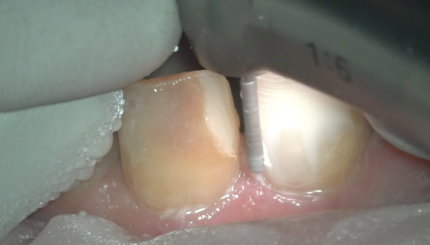

ПРЕПАРИРОВАНИЕ ПОД ВИНИРЫ НА РЕФРАКТОРЕ. 11,21